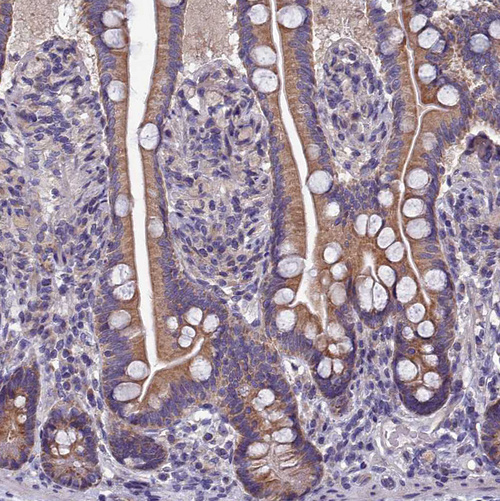

COX20 cytochrome C oxidase assembly factor

Anti-COX20 Antibody

Polyclonal Antibody against HUMAN COX20